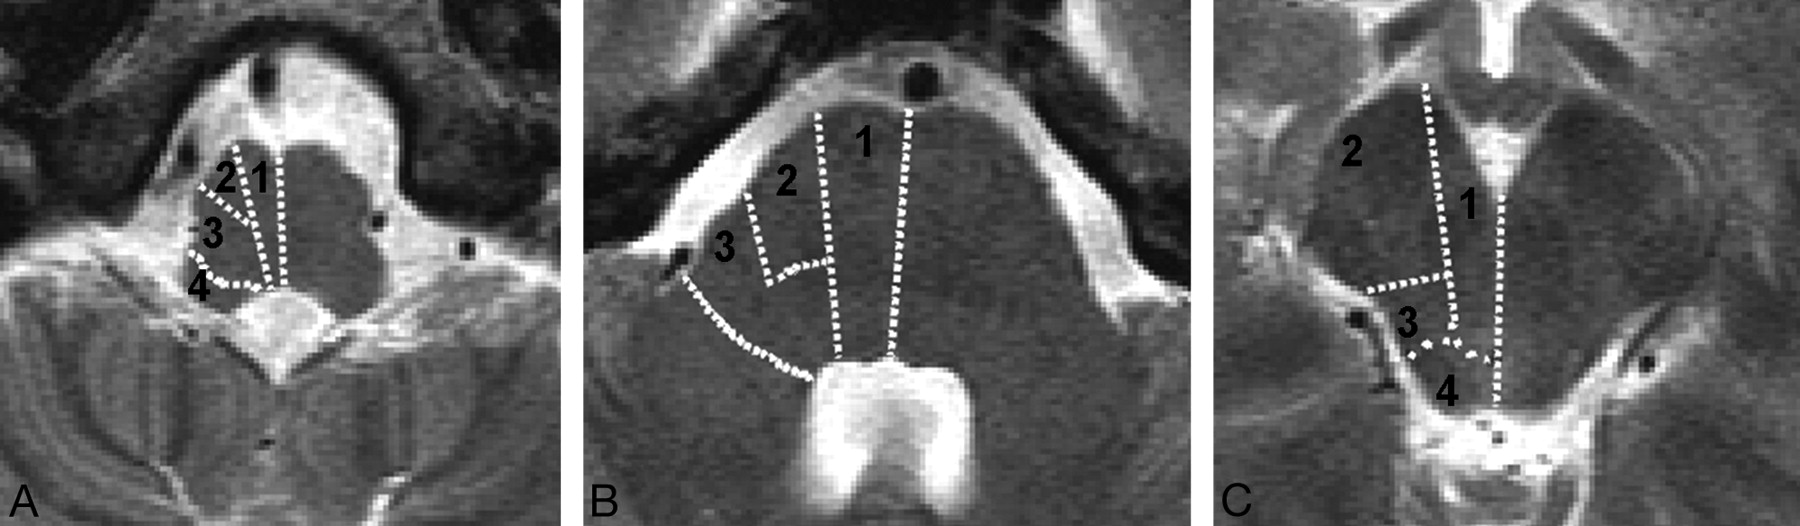

A semiquantitative scale was used to evaluate the extent of the brain stem DWI lesion on pretreatment MR imaging according to the arterial territories of the medulla, pons, and midbrain as described by Tatu et al (Fig 1).22 The number of arterial territories with abnormal DWI was assessed at each brain stem level: 0–8 in the medulla, 0–6 in the pons, and 0–8 in the midbrain. The total number of involved arterial territories defined the brain stem DWI lesion score, comprising scores between 0 and 22. Cerebellar DWI lesions were dichotomized as minor (less than one third of a cerebellar hemisphere) or major (more than one third of a cerebellar hemisphere). MR imaging analysis was done by 2 experienced observers blinded to the severity of the clinical deficit. The interobserver and intraobserver variations were assessed by comparing the differences in measurement 10 days apart on the whole sample. For the discrepant cases, the final scoring of DWI data was achieved by a consensual analysis.

Brain stem DWI lesion score. A, Medulla. B, Pons. C, Midbrain. Arterial segmentation according to Tatu et al22: 1 indicates anteromedial; 2, anterolateral; 3, lateral; and 4, posterior territories. The total number of brain stem arterial territories with abnormal DWI defines the brain stem DWI lesion score, between 0 and 22.